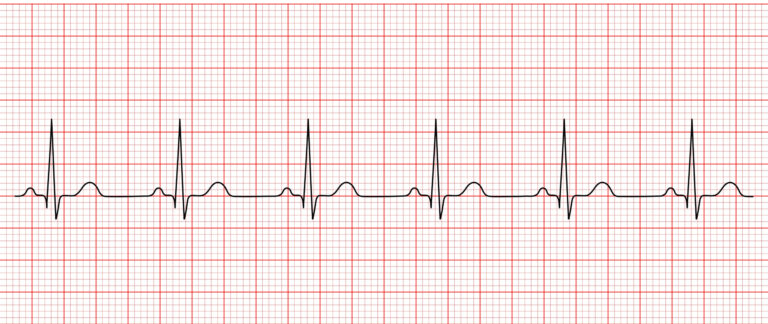

Rekaman EKG menunjukkan Irama Sinus Normal dengan kompleks P-QRS-T yang reguler, termasuk dalam ritme EKG penting yang harus dikenali perawat.

Irama Sinus Normal adalah dasar dari semua irama EKG—reguler, konsisten, dan penting sebagai pembanding dalam penilaian jantung darurat. (Foto oleh JY FotoStock di Shutterstock)

NSR adalah irama yang digunakan sebagai acuan atau dasar untuk membandingkan semua irama lainnya. Perawat harus mengenali pola normal terlebih dahulu sebelum mengidentifikasi perubahan irama yang abnormal atau berbahaya.